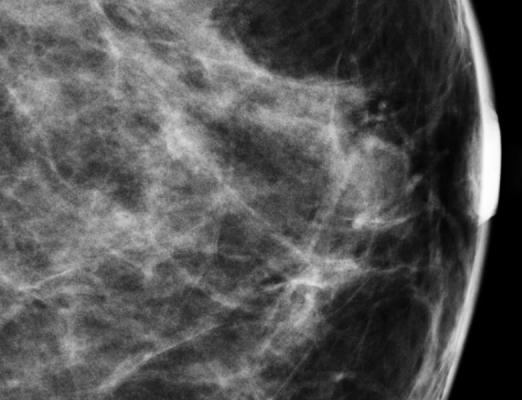

July 16, 2012 — According to a new study by Korean researchers at the Ewha Women's Hospital in Seoul, published this year in the Annals of Nuclear Medicine, molecular breast imaging (MBI), also known as BSGI, may be a better choice than magnetic resonance imaging (MRI) for women who have a new cancer diagnosis and dense breast tissue detected by mammography. According to their results, MBI/BSGI and MRI had nearly the same sensitivity for the detection of additional malignant tumors, but MBI/BSGI was much less likely to be positive in benign lesions.

In their work, Dr. Kim and his colleagues evaluated 66 patients who had a new breast cancer diagnosis and a reported mammography breast density of greater than 50 percent with MBI/BSGI and MRI prior to surgery. Both MBI/BSGI and MRI detected disease not seen by mammography; however, the MBI/BSGI was more accurate than MRI in determining if lesions were benign or malignant.

Only 26 percent of the additional lesions detected by MRI were malignant compared to MBI/BSGI, where 76 percent of the lesions detected were malignant. This is important for the newly diagnosed breast cancer patient since biopsy is required when imaging studies are positive. Therefore, MBI/BSGI could have led to a large decrease in the number of unnecessary biopsies for women in this trial. "The results of this study suggest that MBI/BSGI could play a crucial role as an adjunctive imaging modality which can be used to evaluate breast cancer patients with dense breasts," said Dr. Kim.